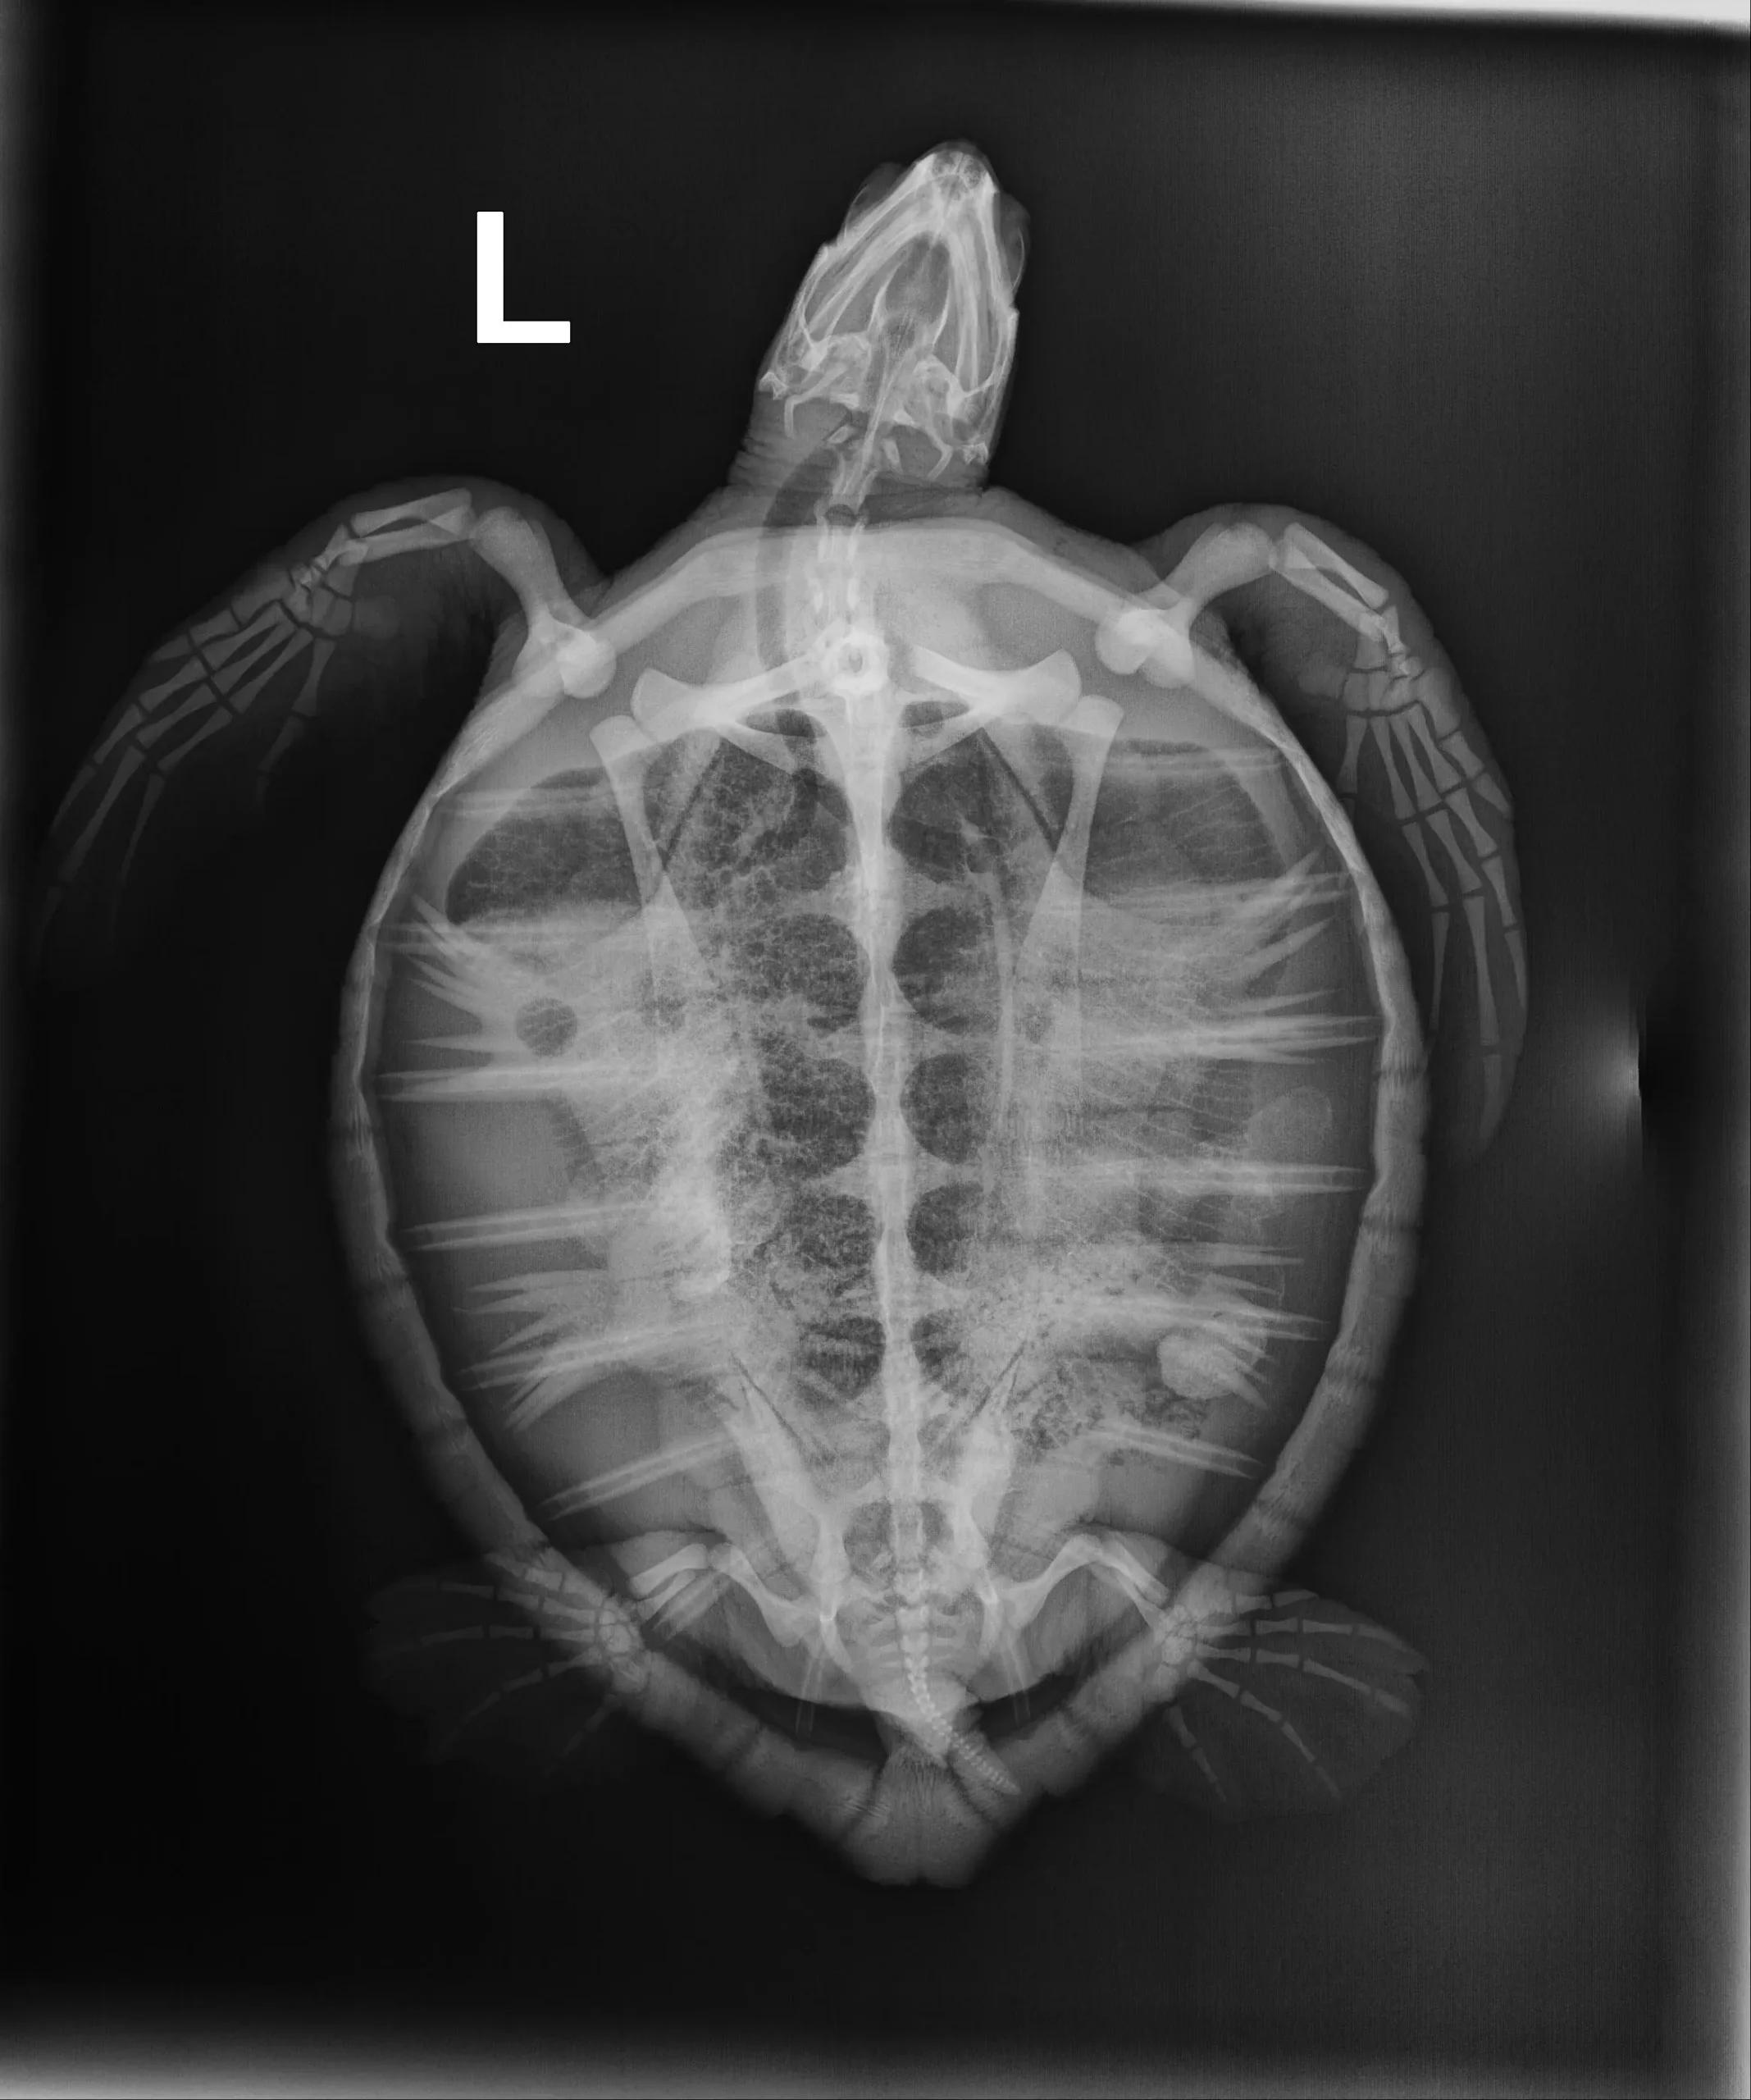

Juvenile Atlantic Green sea turtle and weighs 3.8lbs

Abrasion to the vertebral scutes of the carapace with bone exposure, mild abrasions to the tips of the flippers and plastron.